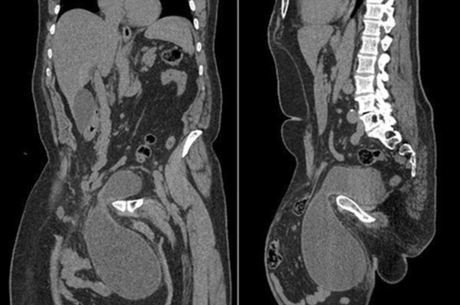

Homem tinha tumor de 30 cm de diâmetro em seu órgão genital

Um homem de 65 anos teve um tumor de tamanho de uma bola de futebol

retirado de seu órgão sexual. Ele decidiu procurar ajuda médica quando

sentiu dificuldade para urinar e para andar, já que o tumor, que crescia

há 12 anos, chegou até à perna. As informações são do site DailyMail.

Os médicos informaram que o tumor tinha cerca de 30 cm de diâmetro, mas o homem não queria operar porque tinha medo que afetasse seu órgão.